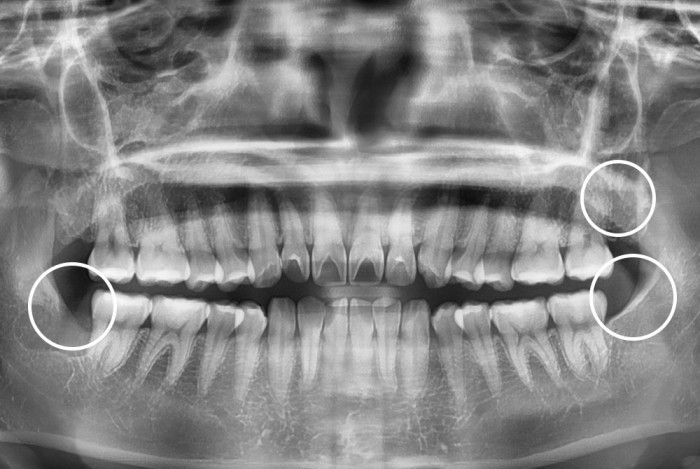

치료후 : 2022-02-25

세종치과는 구강악안면외과학 박사이신 원장님이 발치하는 치과입니다.